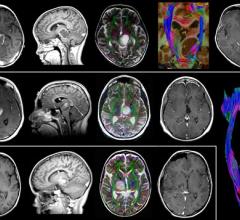

February 2, 2010 - Among noninvasive imaging tests for ruling out coronary artery disease (CAD), computed tomography (CT) is a more accurate noninvasive test than magnetic resonance imaging (MRI), according to a comparative study released in Annals of Internal Medicine.

February 2, 2010 – When doctors added contrast agent gadolinium during magnetic resonance imaging (MRI) they improved primary tumor assessment for detecting lymph node metastases, according to a new study published online February 1, 2010, in the Journal of the National Cancer Institute.